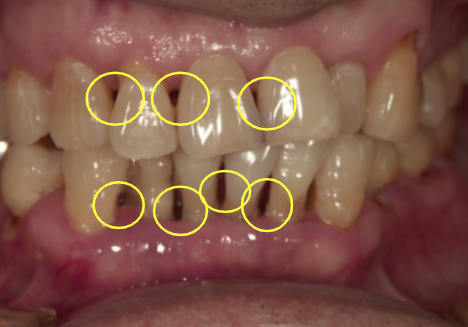

④ 審美不良の進行(見栄えが悪くなる)

- 歯ぐきが下がる

- ブラックトライアングル出現

このように歯と歯の間にすき間が出来てしまい見栄えが悪くなってしまうので女性に不満をあたえてしまう。